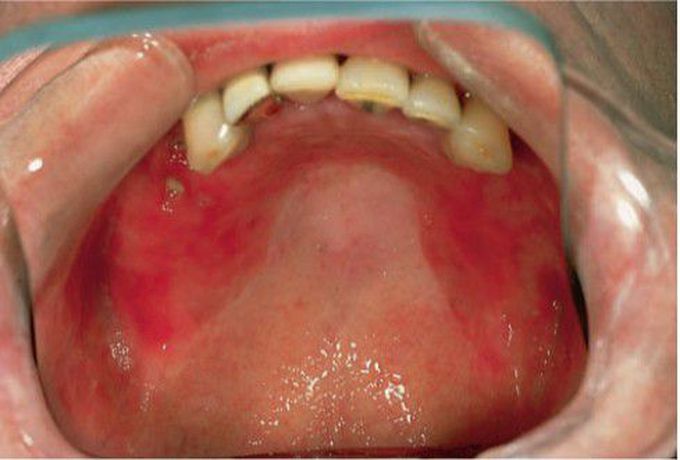

Erythmatous candidiasis

Painful, hyperemic palate under denture; angular cheilitis; red, painful mucosa.

Painful, hyperemic palate under denture; angular cheilitis; red, painful mucosa.